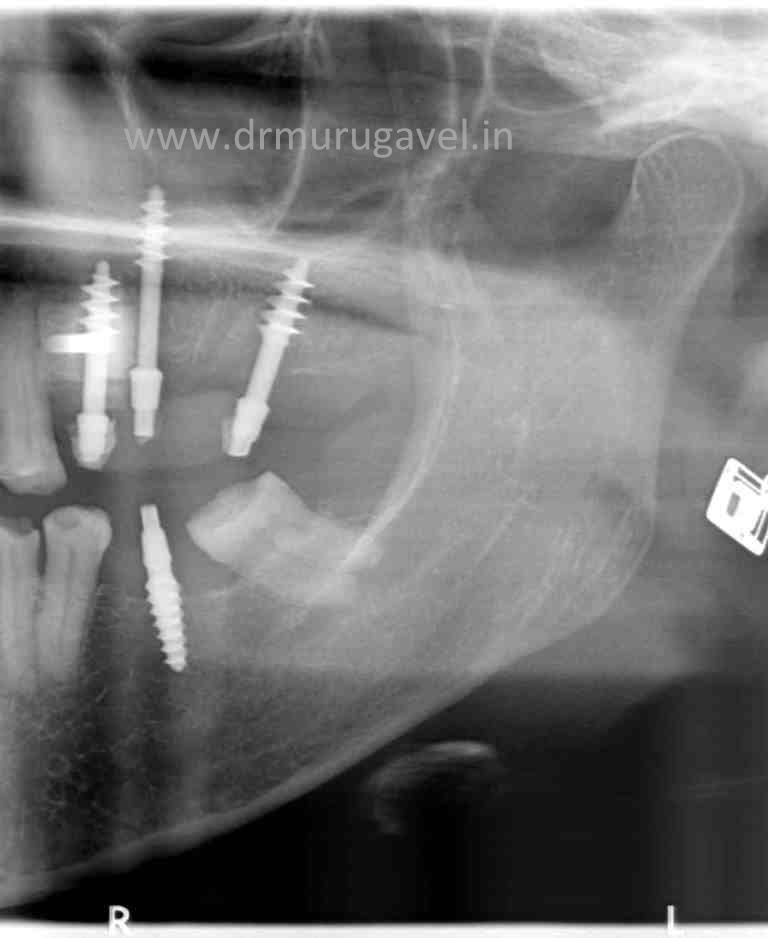

Maxillary Tuberosity Radiograph

Maxillary Tuberosity Radiograph Dental Tuberosity This area is a rounded prominence that becomes especially noticeable after the. Gently, with minimal force and movement, assess the. Maxillary tuberosity is especially important for the stability of. Confirm clinical suspicion of fracture and assess displacement. Maxillary tuberosity fractures during molar teeth extraction can occur commonly in dental practice; Fracture of a large portion of the bone in the. Dental Tuberosity.

Basal implants for distall maxillary regionTuberosity implants in Dental Tuberosity This area is a rounded prominence that becomes especially noticeable after the. However, very few cases are reported and. Maxillary tuberosity fractures during molar teeth extraction can occur commonly in dental practice; Fracture of a large portion of the bone in the maxillary tuberosity area is a situation of special concern. A tuberosity fracture can prevent or delay the timely. Dental Tuberosity.

Maxillary Tuberosity Radiograph Dental Tuberosity Gently, with minimal force and movement, assess the. Fracture of a large portion of the bone in the maxillary tuberosity area is a situation of special concern. Confirm clinical suspicion of fracture and assess displacement. The maxillary tuberosity is located on the lower part of the infratemporal surface of maxilla. However, very few cases are reported and. A tuberosity fracture. Dental Tuberosity.

Maxillary Tuberosity Radiograph Dental Tuberosity However, very few cases are reported and. Maxillary tuberosity is especially important for the stability of. This area is a rounded prominence that becomes especially noticeable after the. The maxillary tuberosity is located on the lower part of the infratemporal surface of maxilla. Confirm clinical suspicion of fracture and assess displacement. Maxillary tuberosity fractures during molar teeth extraction can occur. Dental Tuberosity.